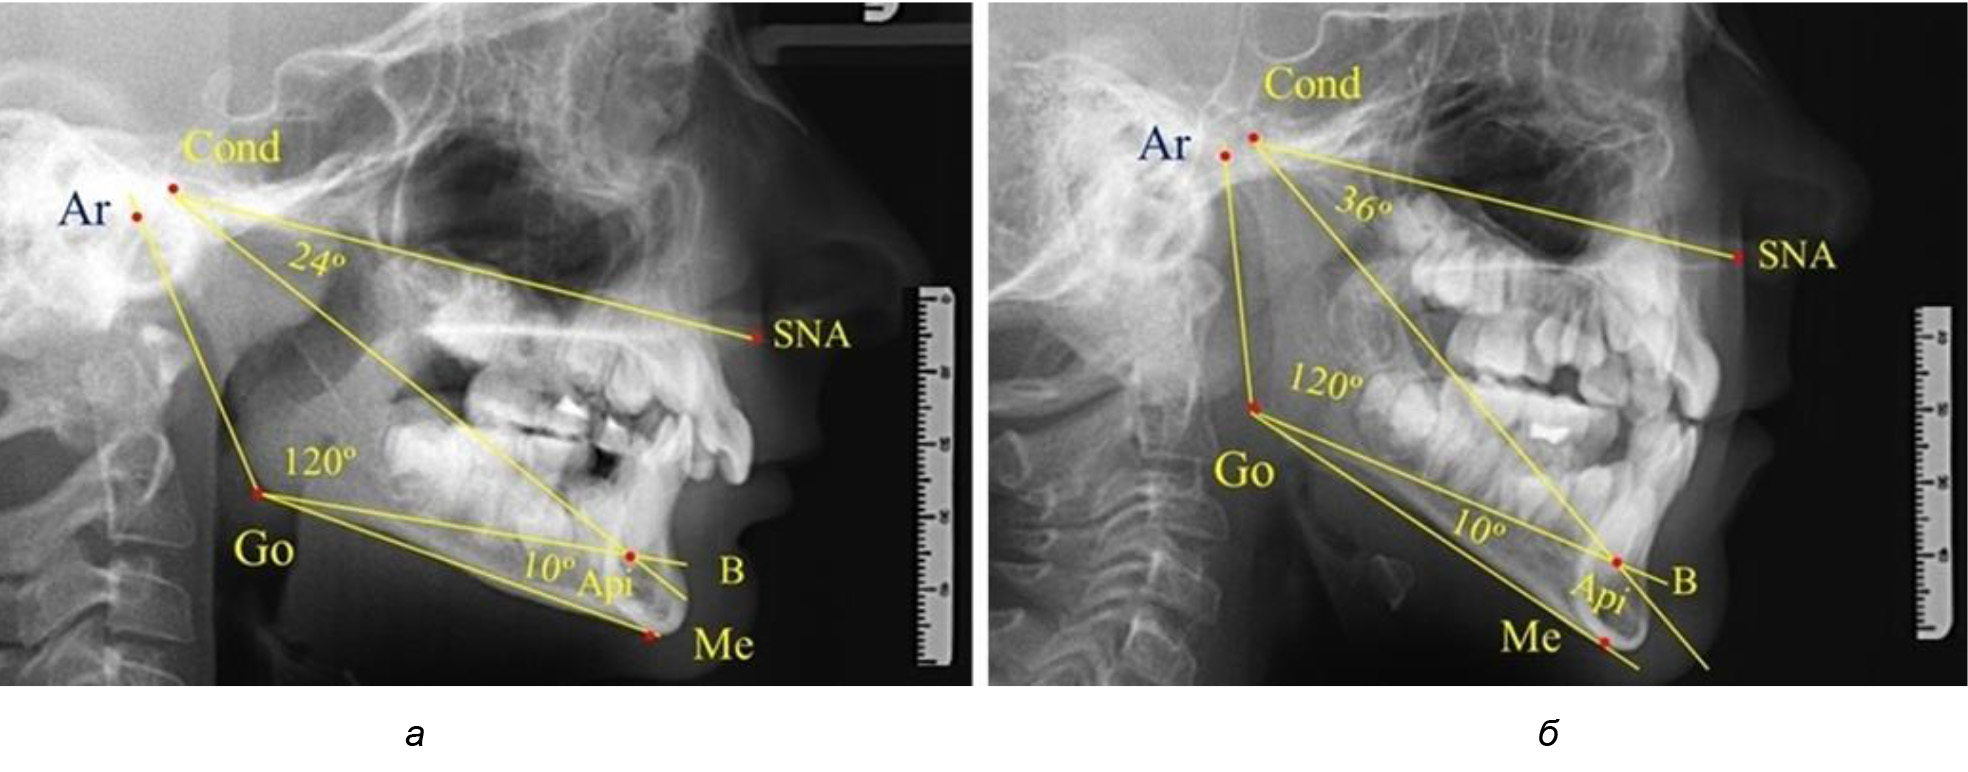

Для горизонтального типа роста было характерно достоверное р ˂ 0,05 уменьшение нижнечелюстного угла до (115,57 ± 0,56)°. Величина угла Ar-Go-Api составила (102,71 ± 1,62)°, а угол Api-Go-Me был (12,86 ± 0,74)° (рис. 3).

Рис. 3. Особенности ТРГ при нейтральном (а), вертикальном (б) и горизонтальном (в) типе угла нижней челюсти в постоянном прикусе

Таким образом, вне зависимости от величины нижнечелюстного угла, показатели угла гнатической части лица были в пределах 30°, что может расцениваться в качестве оптимального физиологического показателя параметров гнатической части лица. Анализ ТРГ проведен у 31 ребенка в различные периоды дентального онтогненеза, включая прикус молочных зубов и различные группы прорезывания постоянных зубов.